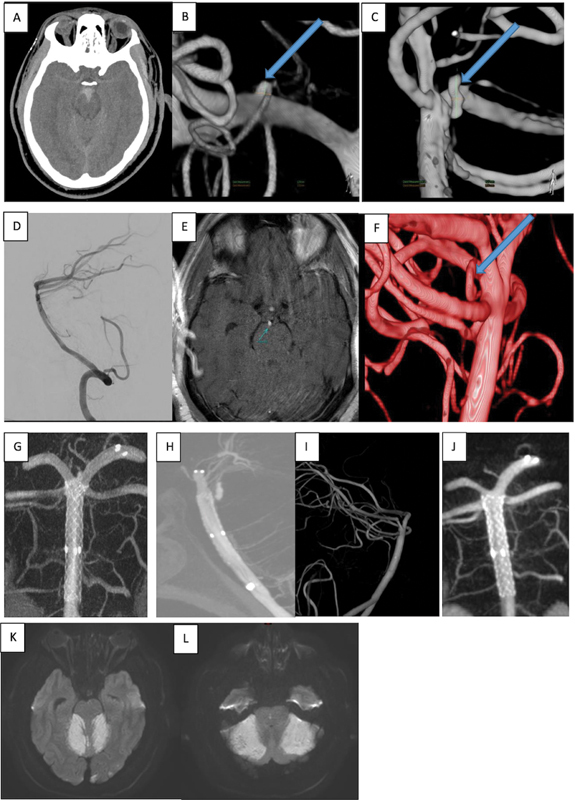

Objectives Subarachnoid hemorrhage (SAH) resulting from rupture of basilar artery perforator aneurysm (BAPA) is a neurological rarity. With increased awareness and advancements in imaging modalities, they are now more frequently detected. However, concerns regarding their suboptimal treatment and lack of proper analysis still exist. We are hereby reporting our experience of treating this entity in a small cohort. Materials and Methods  It is a retrospective study of all the cases of SAH resulting from rupture of BAPA, which were treated by the same surgical team. Demographic data, treatment characteristics, and follow-up data of our cases along with published literature were studied. Results  Our cohort comprised of five patients (mean age 55 years). Three cases were treated with flow diverter alone and the rest underwent flow diverter and overlapping stent placement. Initial diagnostic cerebral angiography (digital subtraction angiography) was negative in three of them. There was one mortality and favorable outcome was encountered in the remaining cases. All of them demonstrated complete occlusion of the aneurysm in follow-up. Conclusion  Following treatment, all the cases demonstrated complete angiographic occlusion of the aneurysm. In available literature, studies have small sample sizes. Future randomized studies in a larger cohort and proper reporting and analysis of outcomes will help us formulating a treatment protocol for BAPA.

Abstract Image